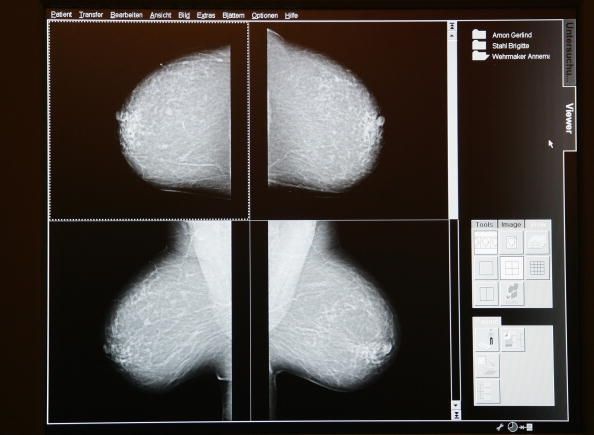

Número de casos de cáncer de mama poco de crecer en un 50% en 2030

El número de casos de cáncer de mama en las mujeres estadounidenses se incrementará en un 50% en 2030. Hubo 283.000 casos diagnosticados en 2011 y, en 15 años se espera que ese número en alrededor de 441.000, según los investigadores del Instituto Nacional del Cáncer.

Philip Rosenberg, un investigador senior del Instituto Nacional del Cáncer, que es uno de los Institutos Nacionales de Salud, dijo que hay tres razones principales para este incremento. Para el 2030, habrá un aumento del número de mujeres que envejecen las mujeres bebé boomers- vivirá vidas más largas, lo que significa que van a tener más años en el que desarrollar cáncer- mama y habrá un aumento en el número de tumores que son el tipo que es receptivo a la hormona estrógeno, un aumento que es probablemente debido a problemas de estilo de vida. En 2030, las mujeres que son mayores de 70 años constituirán una proporción mayor de mujeres que tienen cáncer de mama.

El aspecto positivo de esta nube es que los tumores que son receptivos a los estrógenos, llamados tumores ER-positivos, son mucho más fáciles de tratar que los que no son receptivos a los estrógenos, los tumores ER-negativos. Se espera que el número de tumores ER-negativos a caer en 2030, Rosenberg está reportando. Tumores ER-negativos son el 17% de todos los tumores de mama ahora y se espera que disminuya a alrededor de 9%, pero la razón de esta disminución prevista no se conoce. La proporción de todos los tumores que son ER-positivo ha estado creciendo por razones que incluyen la obesidad, falta de ejercicio, y la exposición a las hormonas, como las píldoras anticonceptivas y la terapia de reemplazo hormonal.

Rosenberg dijo que una de cada ocho mujeres en los Estados Unidos pueden llegar a desarrollar cáncer de mama en algún momento de su vida.